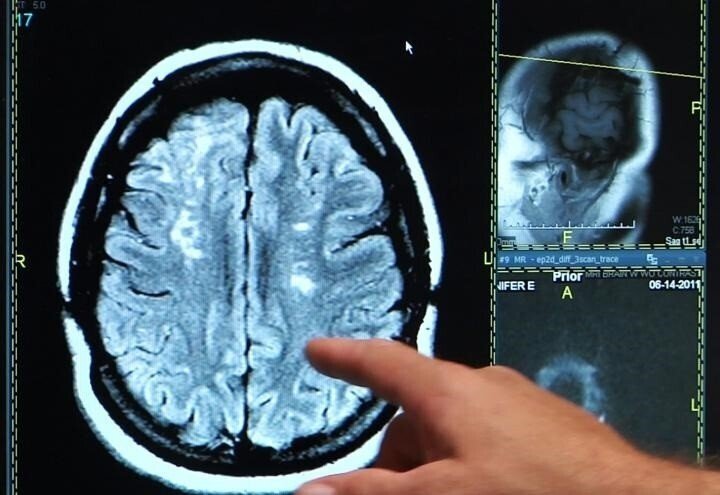

En cuanto al diagnóstico, el estudio de la trombosis venosa cerebral se realiza conjugando la historia clínica (sospecha clínica) y la exploración, junto a pruebas de neuroimagen como el TAC Craneal. "En el 30 por ciento de los casos, el TAC inicial es normal, por lo que se necesita completar con angio-TAC de senos venosos, así como resonancia magnética y angio-resonancia", precisa el especialista.